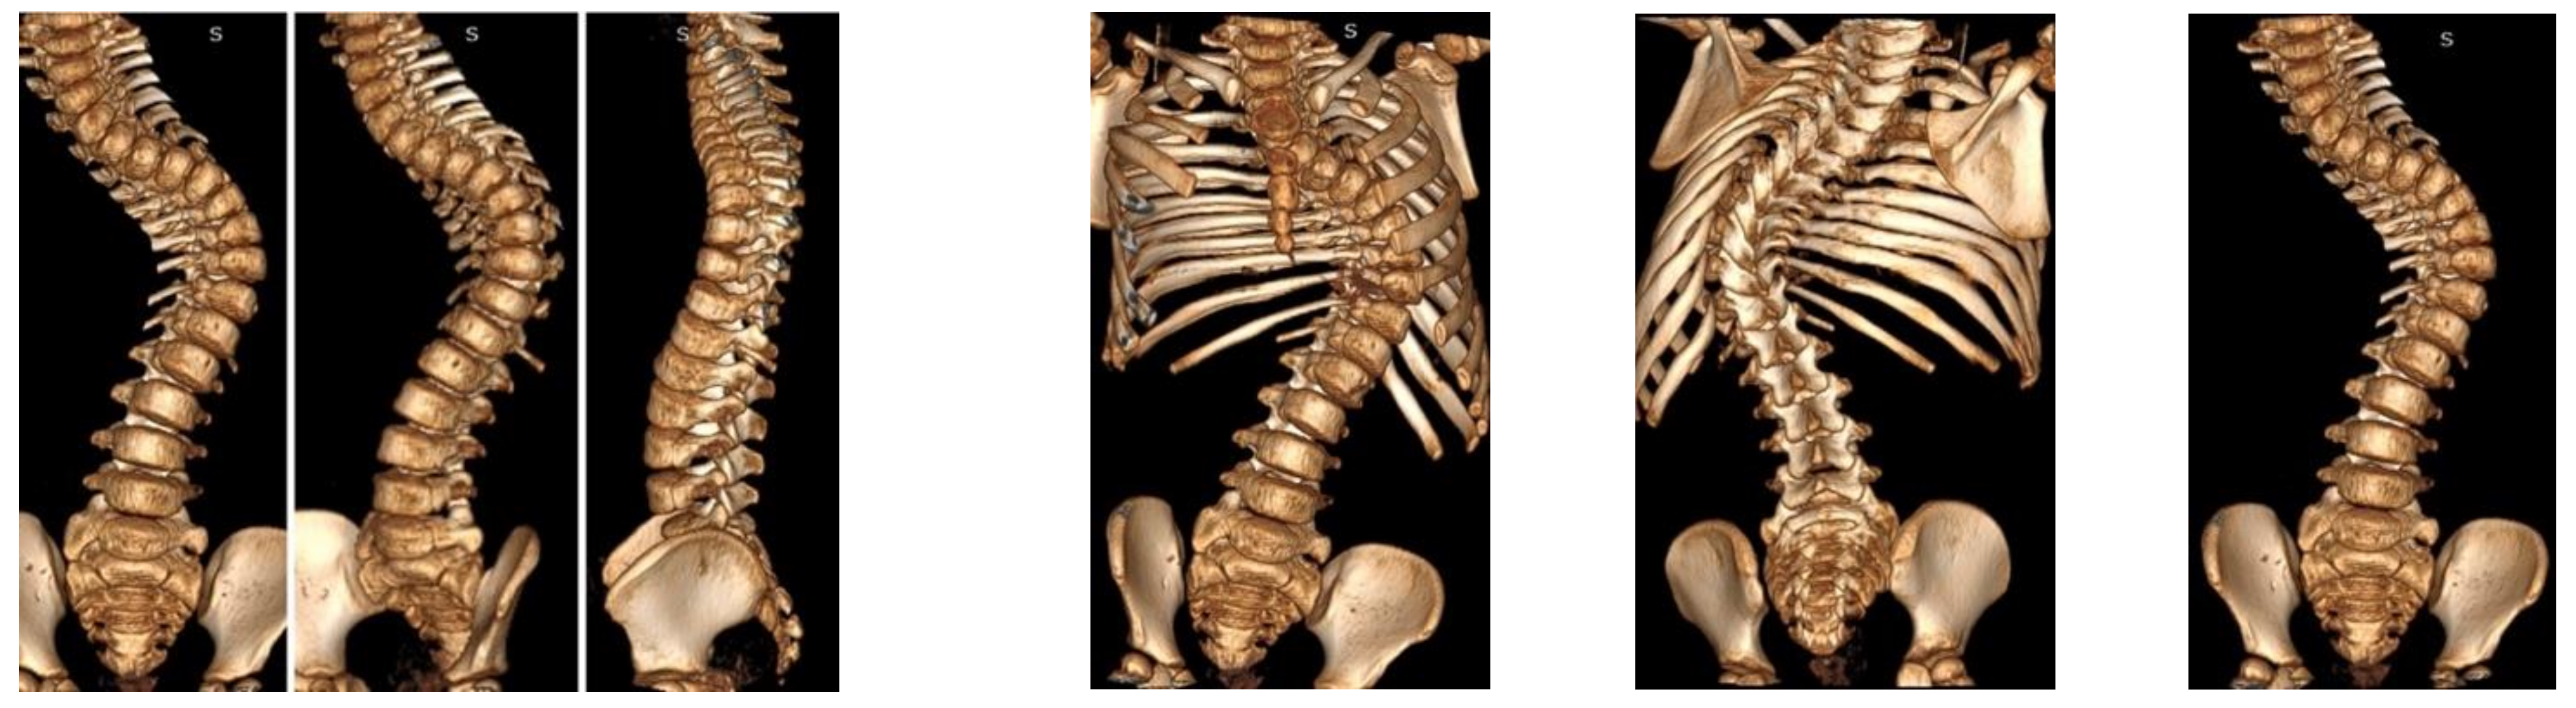

Computed tomography and magnetic resonance imaging were performed. The spinal cord was intact. No other congenital deformities were detected. The patient was born through natural childbirth without any comorbidities (Figure 2).

Figure 2.

CT-3D preoperative images.